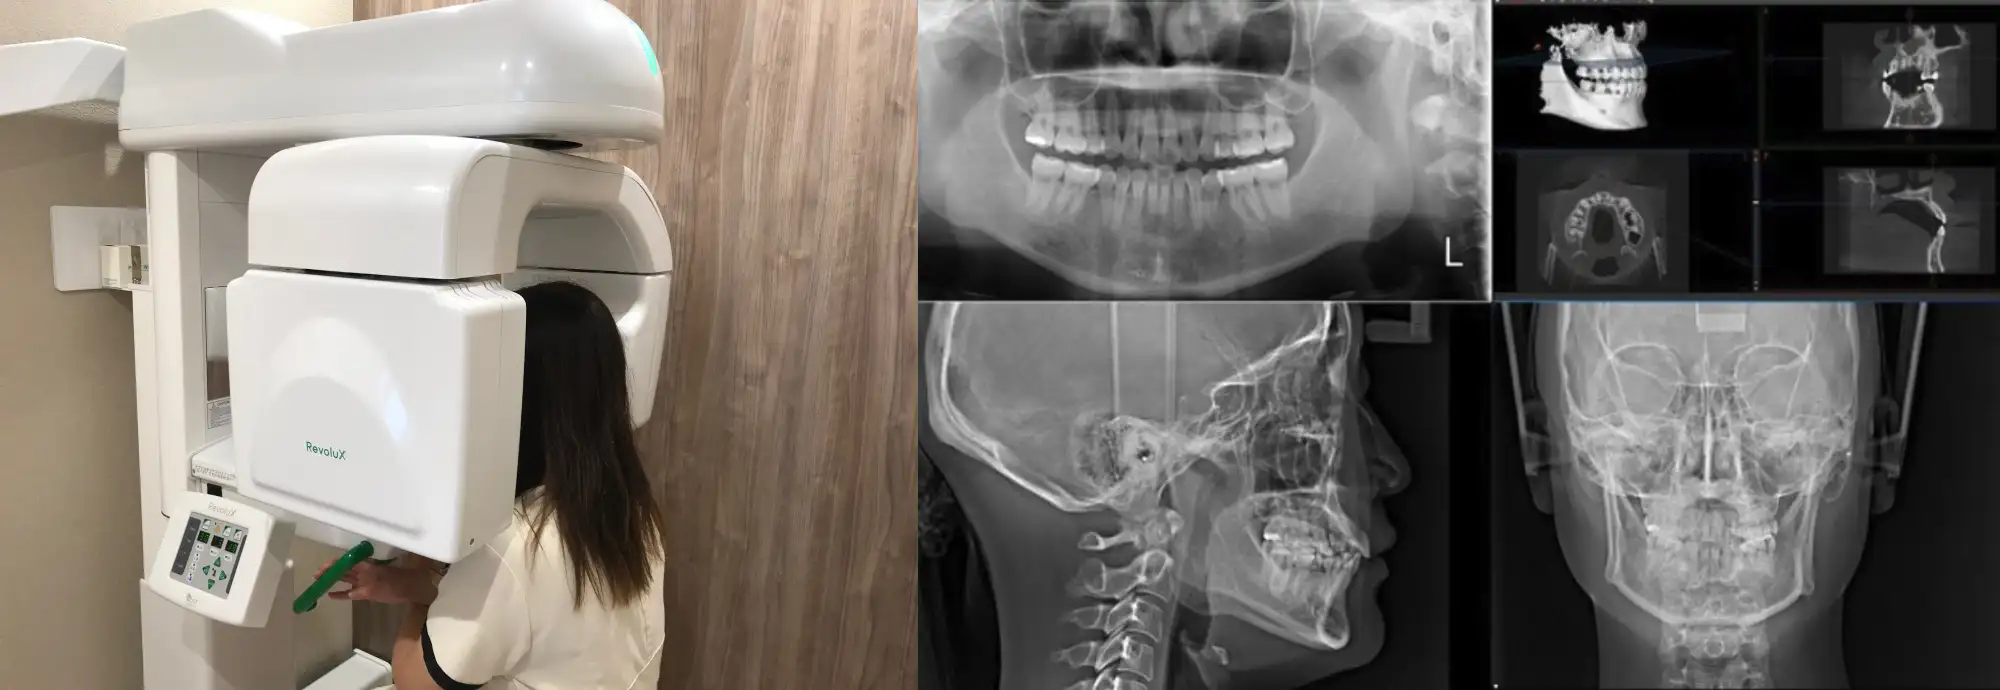

目には見えない骨の幅、量、歯根の長さを治療前に診断することで、より患者様に合った満足度の高い治療方針を導き出します。

当院では歯科用CTを導入しており、従来のレントゲンでは分かりづらかった歯やあごの骨の立体的な形、硬さが把握でき、より高度な治療が可能になりました。

被ばく線量が少ないので、安心してレントゲンをうけて頂けます。